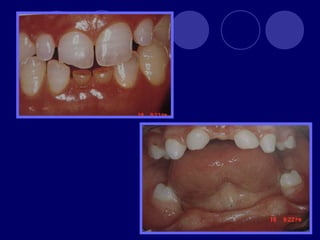

SUPERNUMERARIOS  :aumento enel numero de dientes.

• 11.

 Temporal: 0.5% Permanente: 3%  Maxilar  Masculino  Únicos  Múltiples: Sx. Gardner, disostosis cleidocraneal

FUSIÓN: unión dedos gérmenes (esmalte,dentina),dos cámaras pulpares, más frecuente en la dentición temporal GEMINACIÓN: tentativa fallida de un germen a dividirse (diente con dos coronas y una sola raíz, un solo conducto)